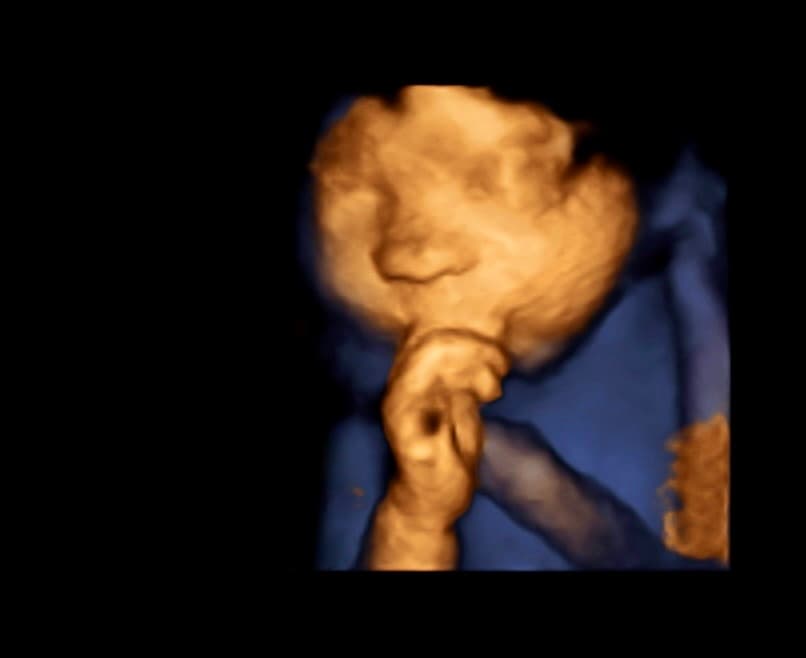

At Magnolia Fetal Imaging, we provide a warm, relaxing environment where you can bond with your baby through advanced 3D/4D & HD ultrasound technology. Our studio focuses on capturing precious keepsake moments for families — gender reveals, early looks, and high‑definition images you will cherish for a lifetime.

All sessions are non‑diagnostic and designed purely for bonding and keepsake entertainment.